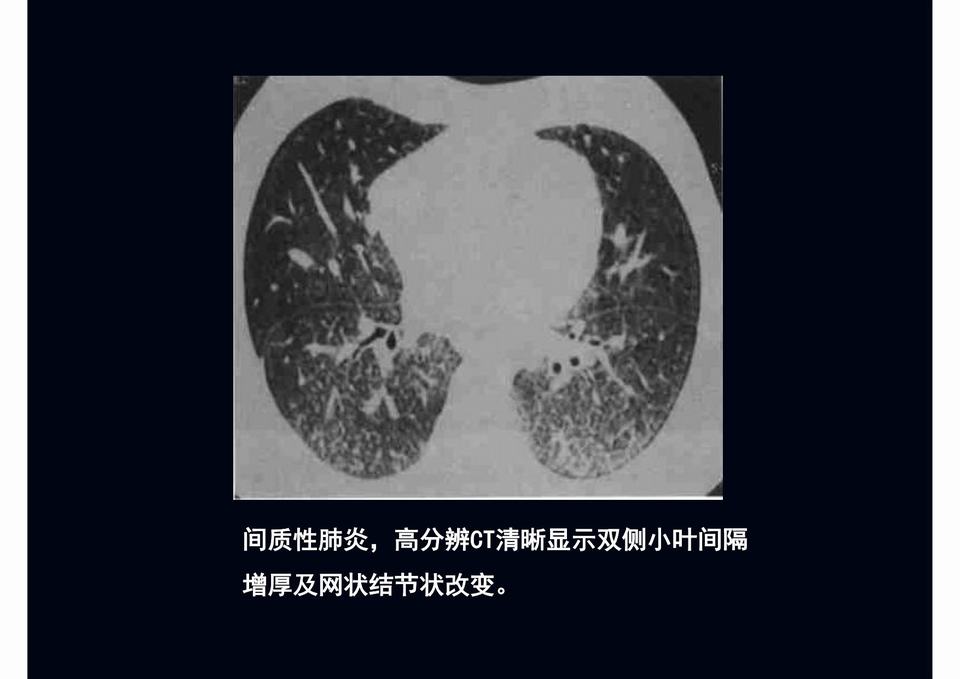

图03